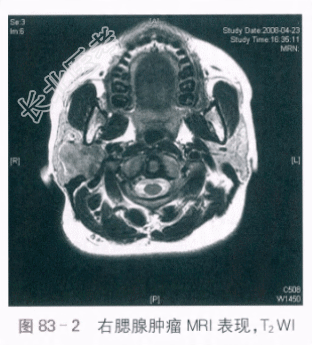

辅助检查:(1)B超检查提示右侧腮腺内见38mm×30mm低回声区,形态规则,边界清,内部回声欠均匀,血流信号少许,双侧腮腺切面形态大小正常,表面光滑,包膜完整,内部回声细小均匀。(2)MRI检查:右侧腮腺区见结节状肿块影,大小约3.7cm×3.2cm×2.4cm,形态不规则,部分伸入下颌后凹,边界尚清,T1WI呈略低信号(见图83-1),T2WI为高低混杂信号(见图83-2)。